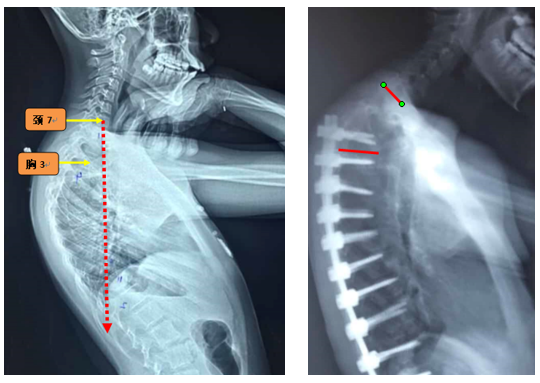

(3)上固定椎位于T1-3

图7 术前-术后1个月-术后1个月外观

Ø 颈7铅垂线距离UIV太远

图19 颈7铅垂线距离UIV太远

图23 选择合适的UIV